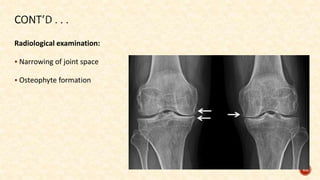

Radiological examination:

 Narrowing of joint space

 Osteophyte formation